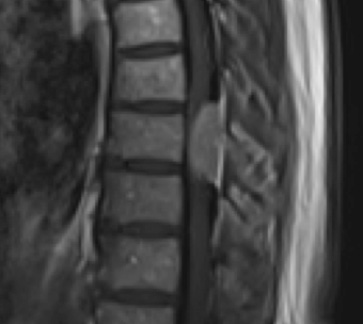

Preoperative MRI T1w demonstrating a large enhancing tumor with severe cord compression

Preoperative MRI T1w demonstrating a large enhancing tumor (red arrow) causing severe cord compression and displacement (blue arrow)